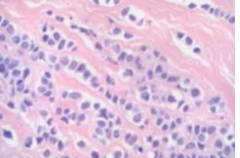

malignant cells showing pleiomorphic, anisocytosic, and discohesive feature

Front

Back